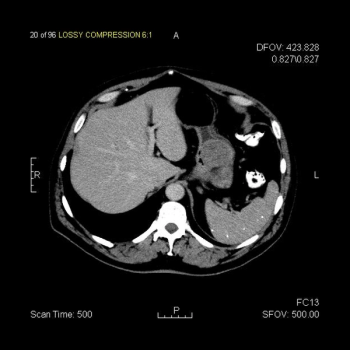

This slide show features a CT image, and pathology images of gastrointestinal stromal tumors (GISTs) arising in the stomach using H&E, CD34, and c-Kit staining.